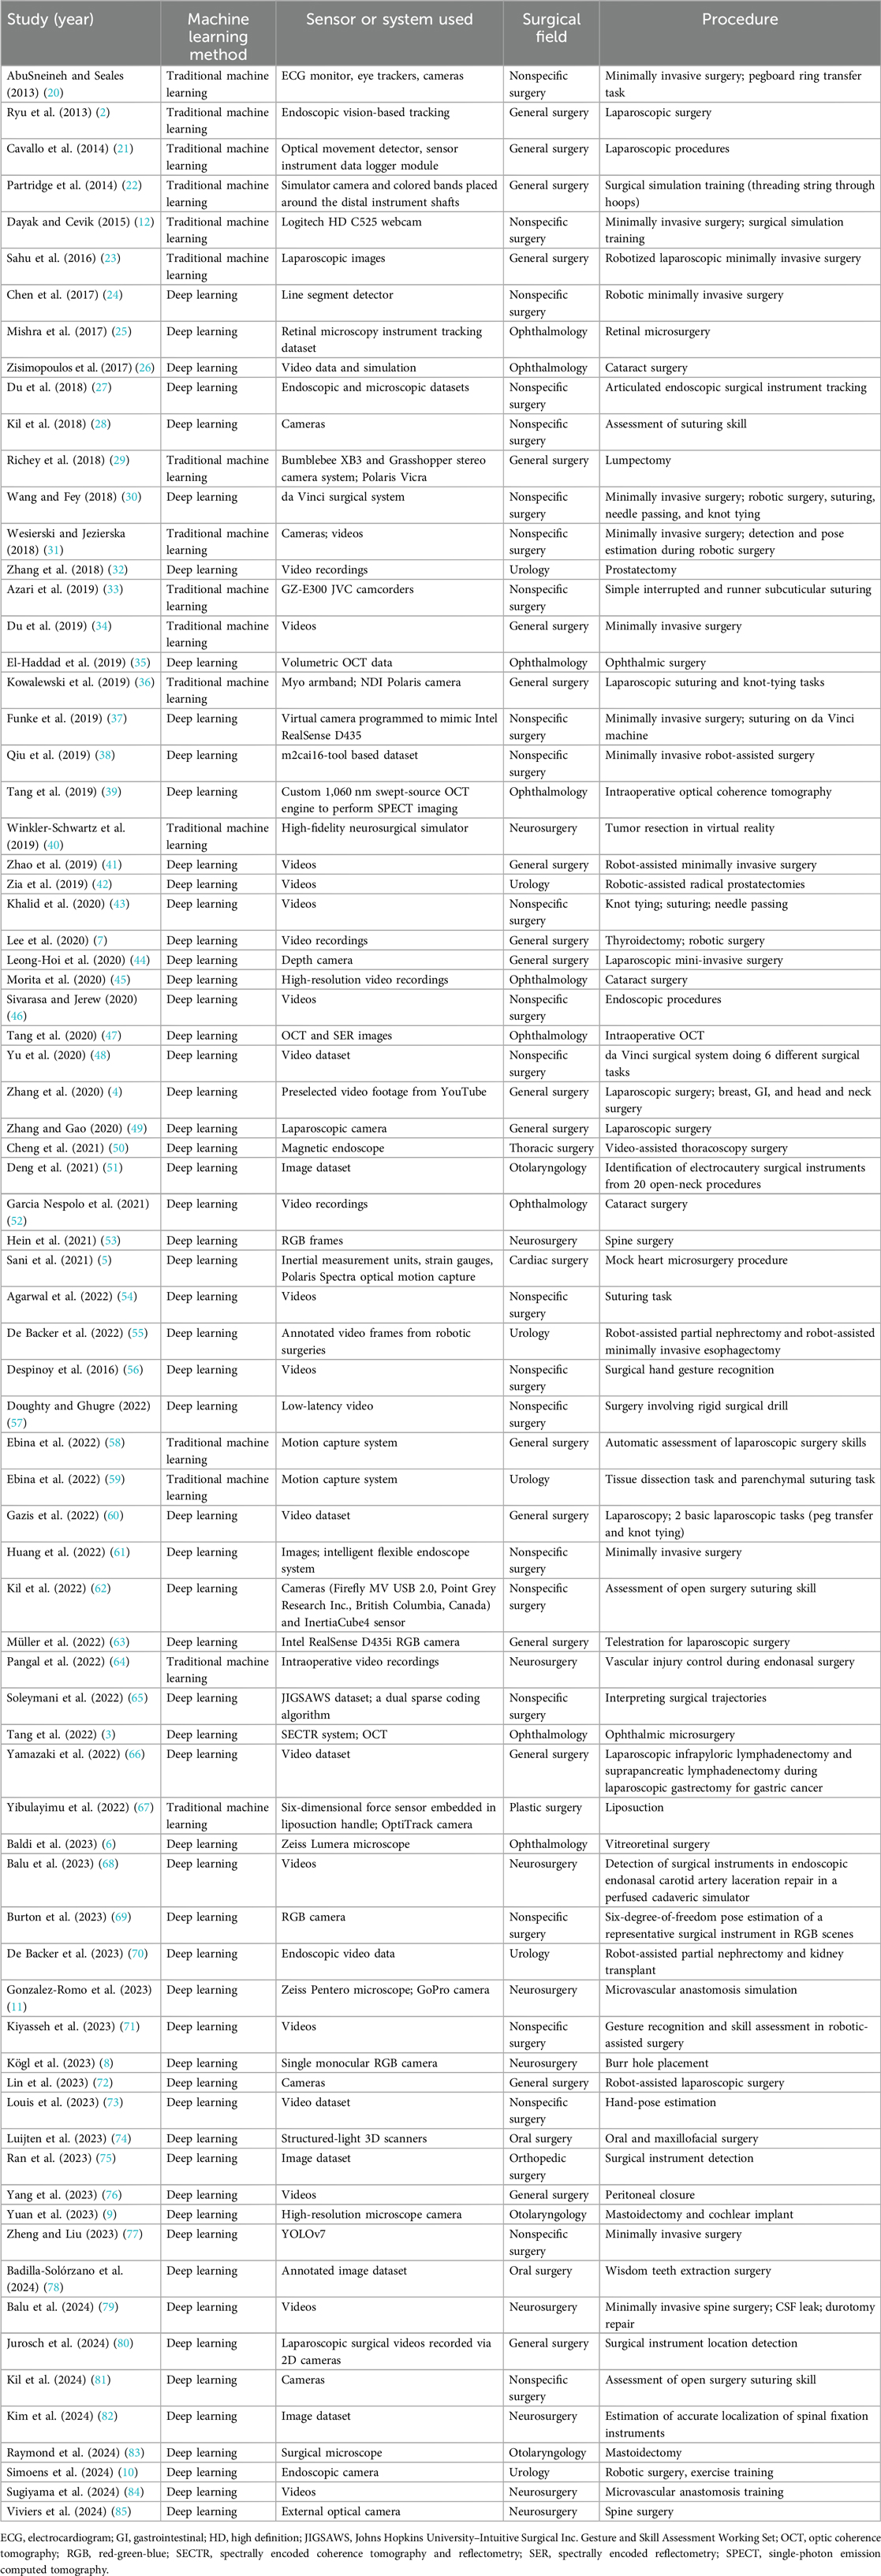

Initially, 225 articles were retrieved. Thirty-five duplicated papers, 21 review articles and editorials, and 5 articles for which the full text was unavailable were excluded. Of the 164 remaining articles, 102 did not meet the inclusion criteria and were excluded. A reference-checking method was performed, and 10 additional articles were found that were within the scope of the study and included. A manual search method was also conducted, and 5 articles were found to be relevant and included in the study. Thus, after screening, a total of 77 articles were found to be eligible for the study and were included (Table 2) (2–12, 20–84). The selection process is documented in Figure 1 (85).

Table 2. Summary of studies focused on applying artificial intelligence algorithms to surgical practice through hand and instrument tracking.